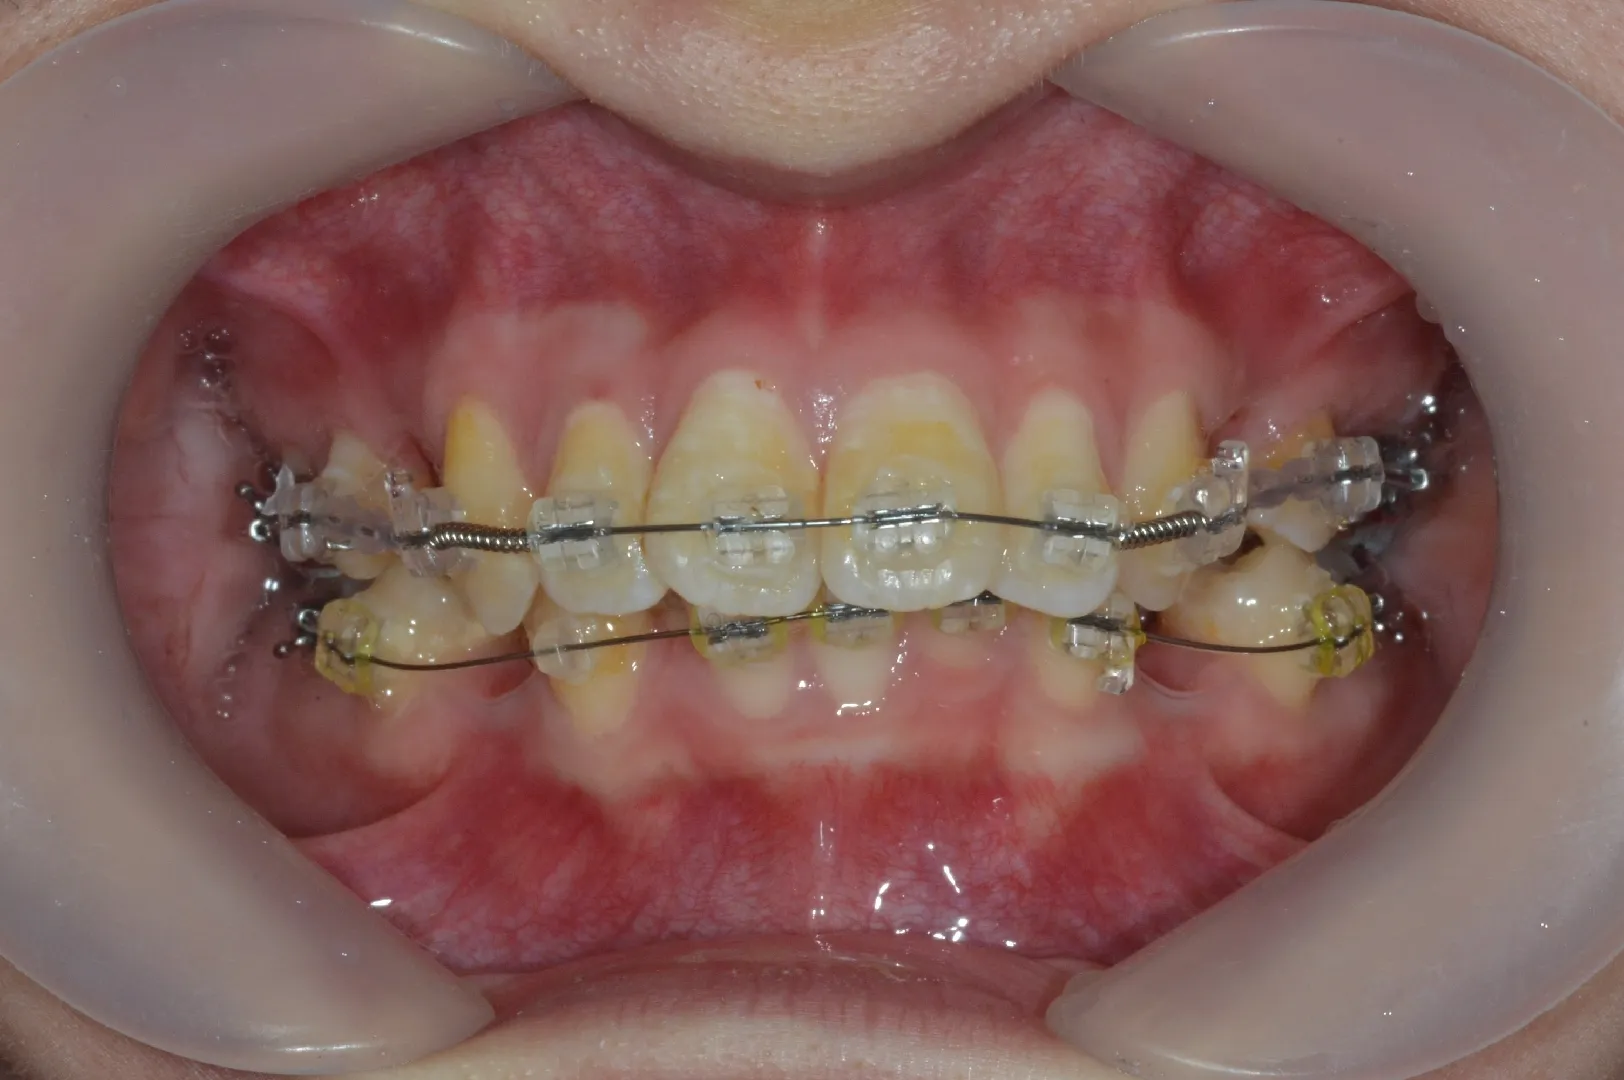

マルチブラケット治療

マウスピース矯正では治療ができないような、重度の不正咬合の場合でも対応可能な治療方法です。当院では患者様にご選択いただくことが最も多い矯正治療方法になります。部分的に矯正治療を行いたい場合(歯並びが悪い箇所が一部の場合など)は一部に取り付けて部分矯正として行っていただくことも可能です。

マルチブラケット治療の流れと治療中に知っておくべきポイント

1.治療開始までのステップ

• セファロなどの検査後、治療計画を決定。

• 抜歯が必要なケースでは先に抜歯を実施

• 奥歯に金属製の「バンド」を装着し固定源を強化。

• その後、各歯にブラケットを接着しワイヤーを通して矯正を開始。

• 初期は来院回数が多く、1か月ほどで調整が落ち着いたら月1回ペースへ。

症例紹介 ― 上下顎前突を伴う成人の抜歯矯正2

前歯の突出と変色(成人女性)

24歳女性。前歯が前方へ大きく傾き、右上前歯の変色も気にされて来院。模型分析・歯列幅の計測・セファロ診断の結果、スペース不足が判明したため上下小臼歯4本を抜歯し、ワイヤー矯正で前歯を後方へ移動しました。抜歯により十分な余裕が生まれ、突出と変色の目立たない自然な口元を実現しています。

症例紹介

• 安全な抜歯スペースの確保

模型分析とセファロ診断でスペース不足を確認し、上下4本の小臼歯を外科的に抜歯。歯周組織を傷つけずに行うことで、矯正後の歯肉退縮リスクを抑えます。

• 固定源の強化

口蓋に沿わせたワイヤー付きバンドで奥歯をがっちり固定。歯周外科的なアプローチで固定源を安定させることで、前歯を効率よく後方へ引っ込められます。

• 長期安定化のサポート

移動後は裏側ワイヤーやマウスピースで後戻りを防止。抜歯部位の歯肉形態を整え、審美性と機能を両立させます。